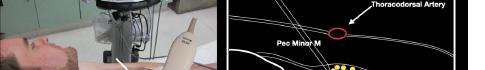

Prior to the start of the procedure, the patient must have IV access and be placed on a cardiac monitor. After informed consent has been obtained, the patient is positioned in the supine position with the head to the contralateral side of the proposed block. The physician stands at the head of the bed above the ipsilateral breast with the ultrasound screen in direct line of sight (commonly at the level of the contralateral hip). The ultrasound probe is initially placed in the sagittal plane at the midclavicular line until the clavicle, pectoralis muscles, and axillary artery and vein are visualized. The transducer is then translated caudally until the third and fourth intercostal spaces are visualized (Image 1).

At this point, the pectoralis major and minor muscles can be visualized. By rotating the transducer 45 degrees clockwise, the thoracoacromial artery can be identified between the pectoralis major and minor muscles. Also, the serratus anterior muscle should be identified resting just above the anechoic rib (Image 2).

Image 1. Initial probe placement for the pectoralis nerve block I and II illustrated on a model: the blue line indicates transducer, and the green dot indicates directional marker corresponding to ultrasound image. Image 2. Final probe placement prior to the pectoralis nerve block I and II: blue line indicates transducer, and green dot indicates directional marker corresponding to ultrasound image.